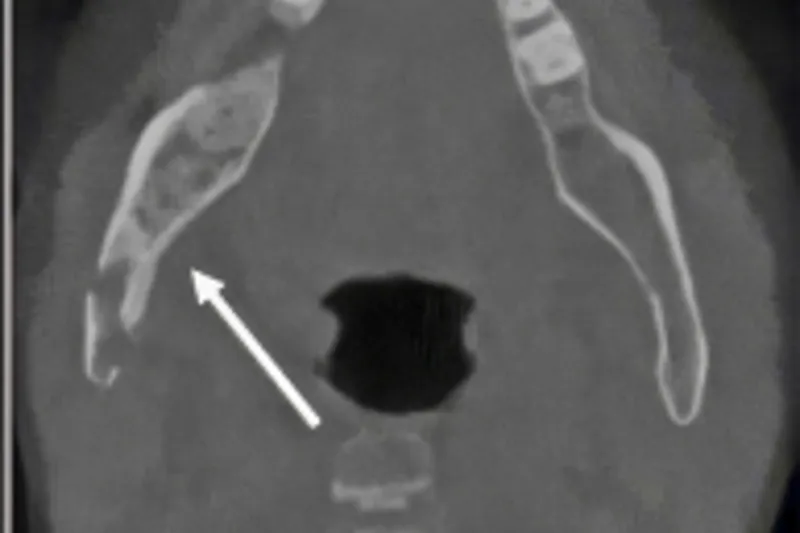

Osteomyelitis er karakteriseret ved en inflammatorisk proces i kæbeknoglen, som oftest er initieret af infektion. Tilstanden kan ses hos både voksne og børn. Sygdommen er ved at blive en relativt sjælden diagnose på grund af bedre mundhygiejne, forbedret tandsundhed og den udbredte brug af antibiotika. Osteomyelitis er en alvorlig og svær tilstand at behandle og er karakteriseret ved smerter, hævelse og i nogle tilfælde også sekvestrering og fraktur af kæbeknoglen. Denne artikel har til formål at give en systematisk gennemgang af sygdommen og dens forløb samt beskrive dens behandling, som den finder sted i hospitalsregi.

Osteomyelitis is characterised by an inflammatory process in the jawbone, which is most often initiated by infection. Osteomyelitis can be seen in both adults and children. The disease is becoming a relatively rare diagnosis due to better oral hygiene, improved health, and the widespread use of antibiotics. Osteomyelitis is a serious condition that is difficult to treat. It is characterized by pain, swelling and in some cases also sequestration and pathological fracture of the jawbone. The purpose of this article is to provide an overview of the disease and to provide general dentists with a knowledge of the treatment strategies is in a hospital setting.